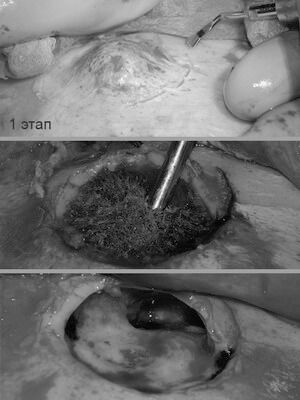

У пациентки выявлена редкая разновидность остеомы - губчатая форма с обширным распространением на лобную кость. Принято решение о косметическом бикоронарном и остеопластическом доступе на лобной кости и лобной пазухе. Разрез спрятан в волосах. Опухоль удалена до твердой мозговой оболочки с , и с местом прорастания в лобную пазуху. Дефект закрыт расщепленным костным аутотрансплантатом с теменной области. Послеоперационное фото сделано на 7 сутки. Отсутствие отеков, гематом, быстрая реабилитация- особенность данной методики.